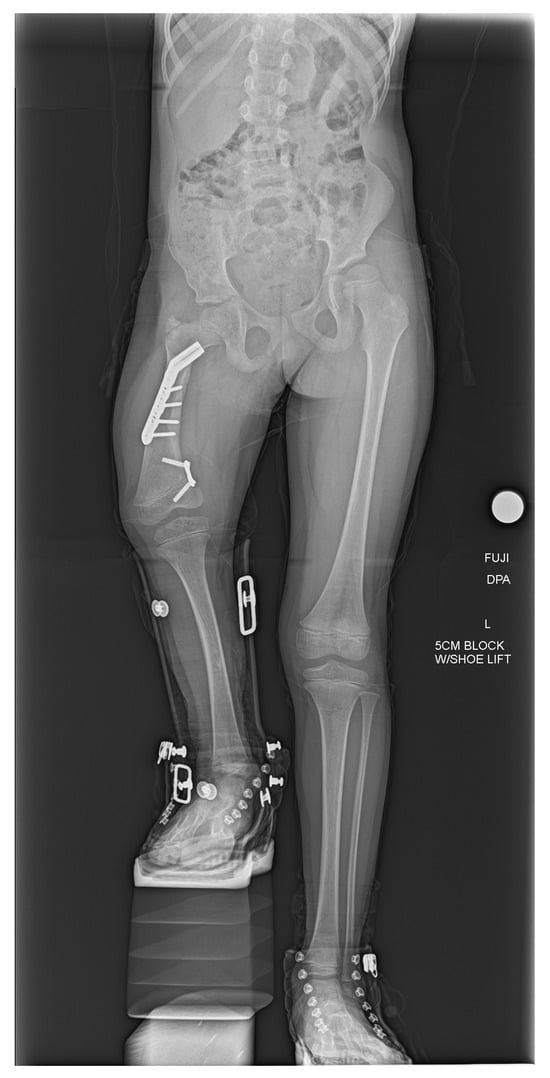

2.1. Case 1